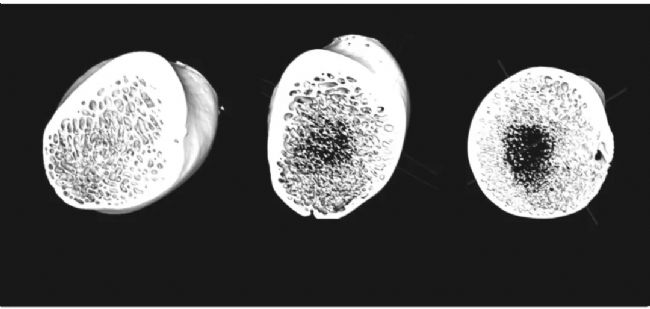

假手術(shù)組(左)與去勢(shì) 4 個(gè)月組(中) 及去勢(shì) 12 個(gè)月 組(右) 腰椎松質(zhì)骨的三維重建圖像。圖片顯示,去勢(shì) 12 個(gè)月組的骨小梁較其他兩組明顯稀疏,孔隙率增加,水平方向骨小梁減少,局部有較大的骨小梁空隙形成。圖片源于文獻(xiàn)【1】。

假手術(shù)組(左)與去勢(shì) 4 個(gè)月組(中)及去勢(shì) 12 個(gè)月 組(右)股骨頸處松質(zhì)骨的三維重建圖像。圖片顯示,去勢(shì) 12 個(gè)月后,股骨頸處松質(zhì)骨有空腔形成,骨小梁明顯變細(xì),皮質(zhì)骨壁變薄。圖片源于文獻(xiàn)【1】。